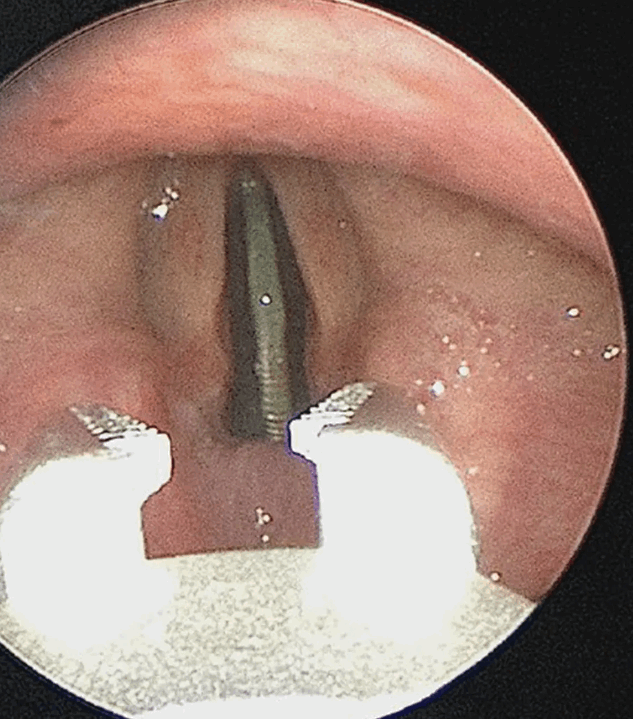

طفل ابتلع 25 سنتاً... وهذه كانت النتيجة! (صور)

طفل ابتلع 25 سنتاً... وهذه كانت النتيجة! (صور)